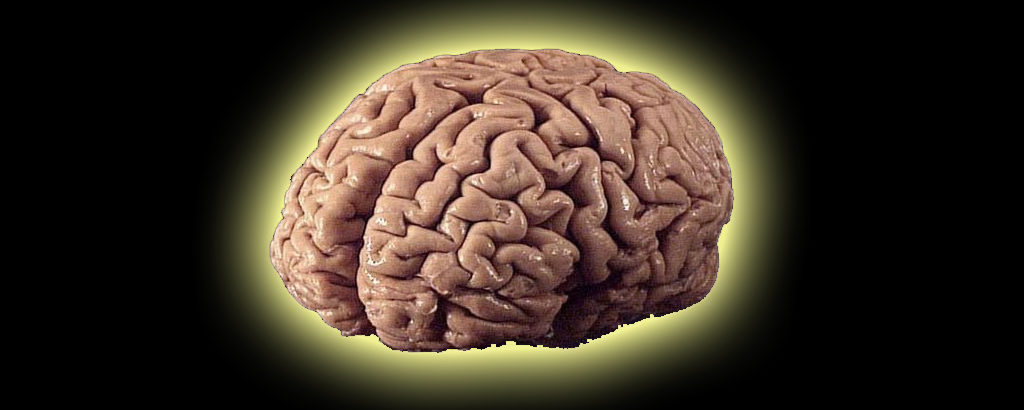

Journalist, author, and CNN medical contributor, Jean Carper, joins us to talk about her documentary film, “Monster In The Mind,” about the myths surrounding Alzheimer’s disease, how dementia is actually on the decline, and how your genes are not necessarily your destiny. Plus, Ralph takes a big bite out of Apple and their trillion-dollar valuation.

Journalist, author, and CNN medical contributor, Jean Carper, joins us to talk about her documentary film, “Monster In The Mind,” about the myths surrounding Alzheimer’s disease, how dementia is actually on the decline, and how your genes are not necessarily your destiny. Plus, Ralph takes a big bite out of Apple and their trillion-dollar valuation.